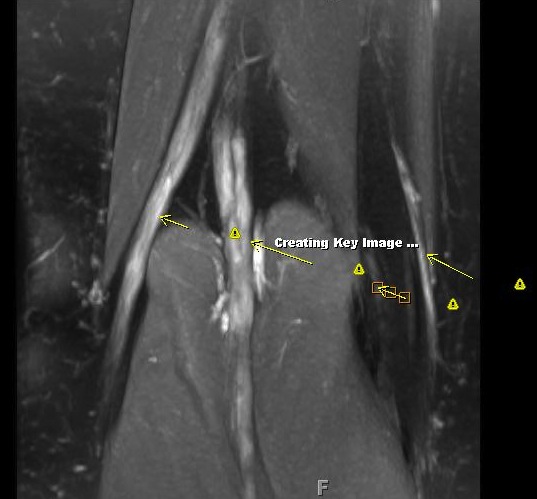

Figure 2 for case Charcot Marie Tooth Type 1a

Figure 2